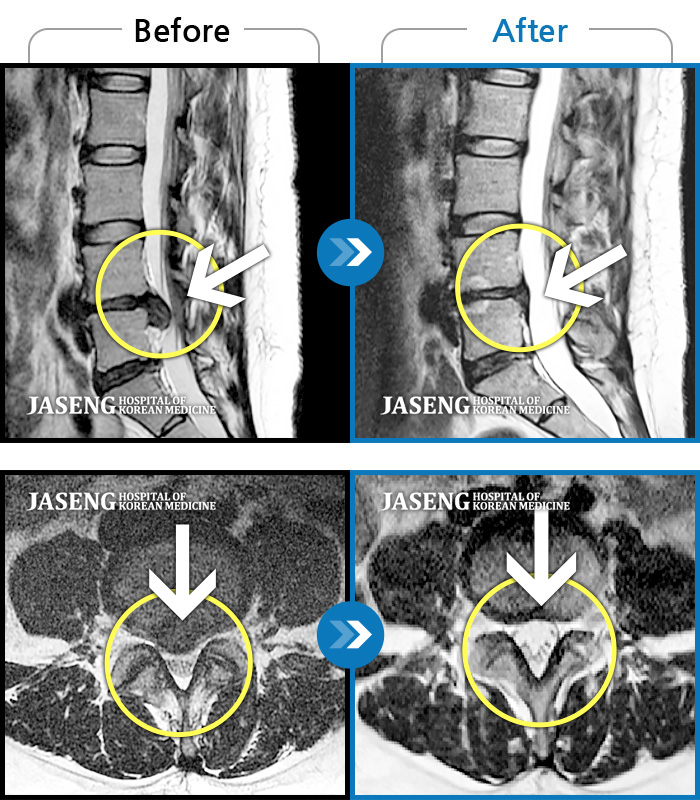

컴퓨터 모니터로 많이 튀어나온 디스크도 쑥 들어간 mri사진 사례들을 여러개 보여주시며 이보다 더 많은 사례가 있다고 제게 희망을 주셨습니다